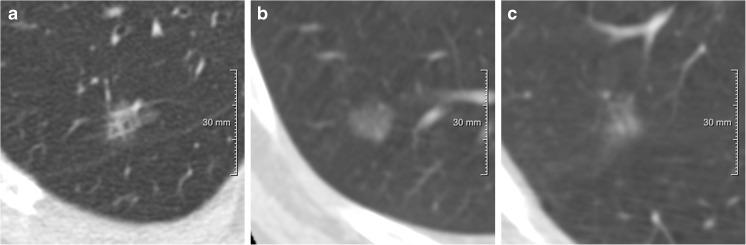

CT 上亚实性结节 Lung-RADS 标准的恶性估计:使用 NLST 结节时低风险和高风险谱的准确性。

Malignancy estimation of Lung-RADS criteria for subsolid nodules on CT: accuracy of low and high risk spectrum when using NLST nodules.

Lung-RADS proposes malignancy probabilities for categories 2 (<1%) and 4B (>15%). The purpose of this study was to quantify and compare malignancy rates for Lung-RADS 2 and 4B subsolid nodules (SSNs) on a nodule base.

We identified all baseline SSNs eligible for Lung-RADS 2 and 4B in the National Lung Screening Trial (NLST) database. Solid cores and nodule locations were annotated using in-house software. Malignant SSNs were identified by an experienced radiologist using NLST information. Malignancy rates and percentages of persistence were calculated.

Of the Lung-RADS 2SSNs, 94.3% (1790/1897) could be located on chest CTs. Likewise, 95.1% (331/348) of part-solid nodules ≥6 mm in diameter could be located. Of these, 120 had a solid core ≥8 mm, corresponding to category 4B. Category 2 SSNs showed a malignancy rate of 2.5%, exceeding slightly the proposed rate of <1%. Category 4B SSNs showed a malignancy rate of 23.9%. In both categories one third of benign lesions were transient.

Malignancy probabilities for Lung-RADS 2 and 4B generally match malignancy rates in SSNs. An option to include also category 2 SSNs for upgrade to 4X designed for suspicious nodules might be useful in the future. Integration of short-term follow-up to confirm persistence would prevent unnecessary invasive work-up in 4B SSNs.

• Malignancy probabilities for Lung-RADS 2/4B generally match malignancy risks in SSNs. • Transient rate between low-risk Lung-RADS 2 and high-risk 4B lesions were similar. • Upgrade of highly suspicious Lung-RADS 2 SSNs to Lung-RADS 4X might be useful. • Up to one third of the benign high-risk Lung-RADS 4B lesions were transient. • Short-term follow-up confirming persistence would avoid unnecessary invasive work-up of 4B lesions.